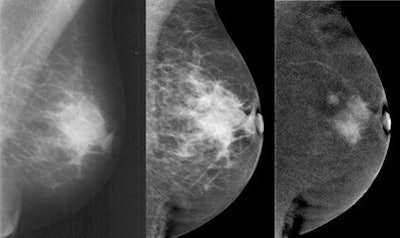

The study was approved by the German governmental Health Authorities and Ethics Committee, and included 68 patients with biopsy-proven breast cancer. Contrast-enhanced digital mammography was performed as a bilateral mammogram (Senographe DS, GE Healthcare), starting two minutes after injection of 1.5 mL/kg of an iodinated contrast agent (300 mg/mL) with a flow of 3 mL/sec. Contrast-enhanced digital mammography and mammography images were interpreted by three blinded independent radiologists with an interval of four weeks for memory washout.

The researchers found 23 false negatives in mammography. There were three false negatives in the combination (mammography plus contrast-enhanced mammography) and two false negatives in contrast-enhanced mammography alone. Sensitivity was 87.6 % for mammography, 97.4% for contrast-enhanced mammography, and 92.3% for the combination.

"Contrast-enhanced digital mammography alone showed equal detection and sensitivity for the index cancer than the combination with mammo," Fallenberg concluded. "It is superior to mammo alone in lesion detection, and there was no significant difference in size evaluation between all the three modalities. So I would say in symptomatic patients we can start with contrast-enhanced mammography alone upfront and save 50% of the radiation dose."